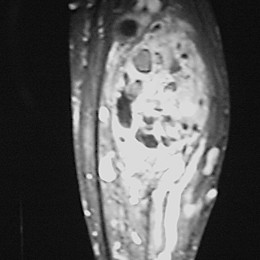

Radiographic imaging is used to help form a diagnosis. These include X-Ray, MRI, CT and Bone Scans.

An example of an MRI is shown.